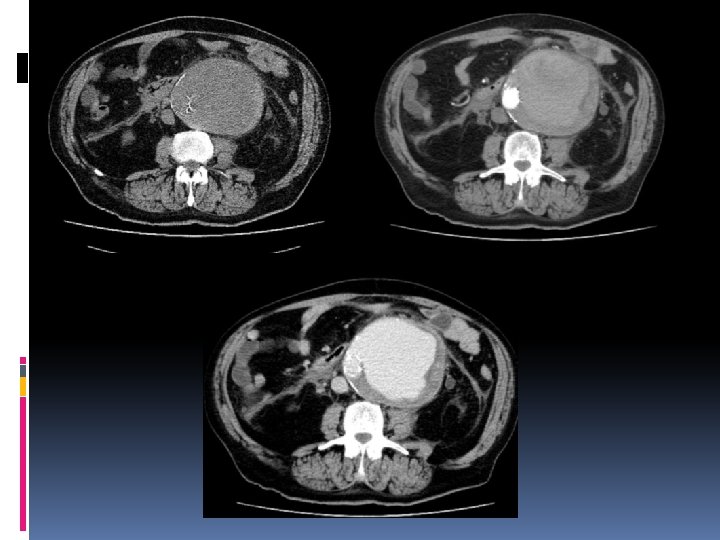

Rotura de Aneurisma Abdominal Dolor Abdominal en espalda y flanco izquierdo+ Hipotensión + Masa Abdominal Pulsátil. Pruebas de Imagen: Ecografía (si el paciente no mantiene ls Costantes vitales) Angio-CT

Hallazgos radiológicos Aneurisma habitualmente grande. Solución de continuidad en pared arterial, calcificaciones o trombo. Hematoma periaórtico que se extiende a espacios pararrenal y perirrenal. . Desviación del hematoma hacia lado izdo. Irritación del psoas. Hemorragia activa, extravasación de contraste. Tejido inflamatorio periaórtico.

Protocolo para CT Estudio basal desde xifodes a pubis. Cortes de 5 mm. Estudio en fase arterial: Sure Star Delay Fijo. Estudio en fase venosa o tardío. 120 -150 cc de contraste, 3 -5 cc/s. Valorar administración de contraste bifásica. Reconstrucciones MPR y MIP.

Datos para el informe De urgencia: Definir si hay o no ruptura. Supra o infrarrenal. Diámetro max. del aneurisma. En aneurismas no rotos: Distancia desde las arterias renales al aneurisma. Diametro axial 1 cm superior al aneurisma. Diametros de ambas iliacas. Diametro longitudinal máximo (MPR curvo)

Signos de ruptura inmimente “Signo de la semiluna de hiperatenuación” : Sangre que diseca de forma aguda el trombo intraluminar, se evidencia mejor sin contraste o en fase tardia.